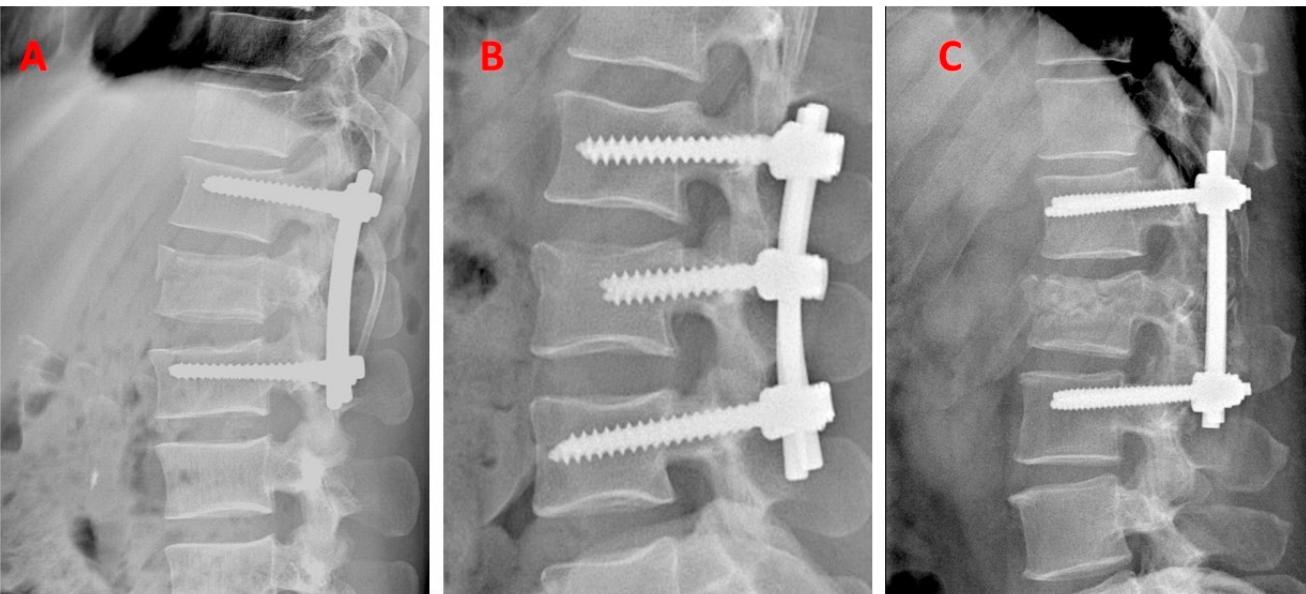

Surgical Fixation Techniques

Stabilization Methods:

- Skin/Skeletal traction

- Surgery ± Decompression

Surgical Management

Indications:

- Unstable with/without neurological injury

- Progressive neurological deficits